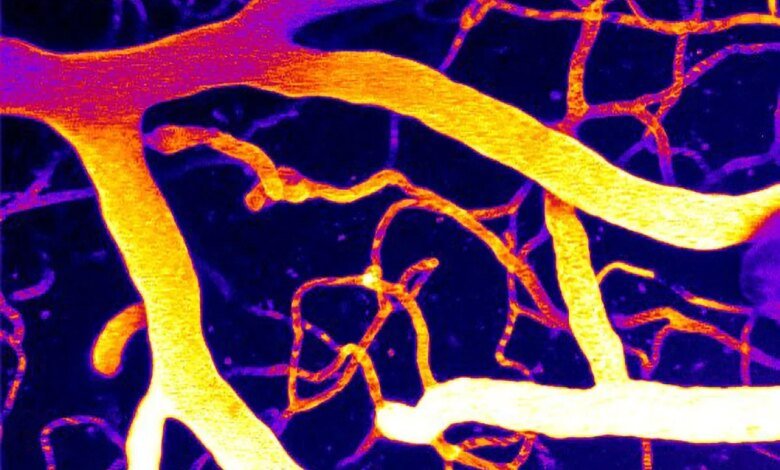

بدأ يظهر نهج جديد محتمل لعلاج انخفاض تدفق الدم في الدماغ وأشكال الخرف ذات الصلة. العلماء في جامعة فيرمونت كشف روبرت لارنر، دكتوراه في الطب بكلية الطب، عن تفاصيل جديدة حول كيفية تنظيم تدفق الدم في الدماغ، مشيرًا إلى طريقة محتملة لإصلاح المشكلات في نظام الأوعية الدموية في الدماغ.

يدرس مختبر حراز كيفية التحكم في تدفق الدم في الدماغ، مع التركيز على إشارات الأوعية الدموية والبروتين المستشعر للضغط المسمى Piezo1 الموجود في خلايا الأوعية الدموية.

تظهر النتائج الجديدة أن Piezo1 يلعب دورًا مهمًا في تنظيم تدفق الدم الدماغي وأن أمراض مثل مرض الزهايمر ترتبط بنشاط Piezo1 المرتفع بشكل غير طبيعي في الأوعية الدموية في الدماغ.